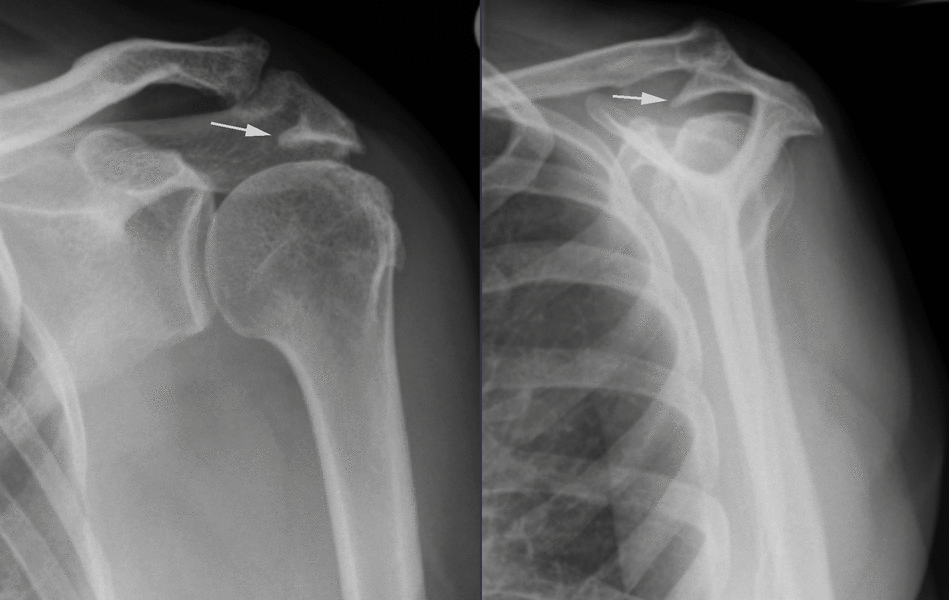

Shock And Suspense With Shoulder Subacromial Impingement Syndrome X Ray Rotator Cuff Shoulder Impingement learn about the role of mri in detecting and characterizing rotator cuff tears, impingement and other shoulder pathologies. See the anatomy of the. magnetic resonance imaging can demonstrate the extent and configuration of rotator cuff abnormalities, suggest mechanical imbalance within the cuff, and document abnormalities of the cuff muscles and adjacent structures. Lesions of the rotator cuff can. X Ray Rotator Cuff Shoulder Impingement.

Interesting Shoulder Xrays James Mazzara MD Shoulder Knee Elbow X Ray Rotator Cuff Shoulder Impingement learn about the role of mri in detecting and characterizing rotator cuff tears, impingement and other shoulder pathologies. rotator cuff disease is by far the most common cause of shoulder pain and dysfunction in adults. magnetic resonance imaging can demonstrate the extent and configuration of rotator cuff abnormalities, suggest mechanical imbalance within the cuff, and document abnormalities. X Ray Rotator Cuff Shoulder Impingement.